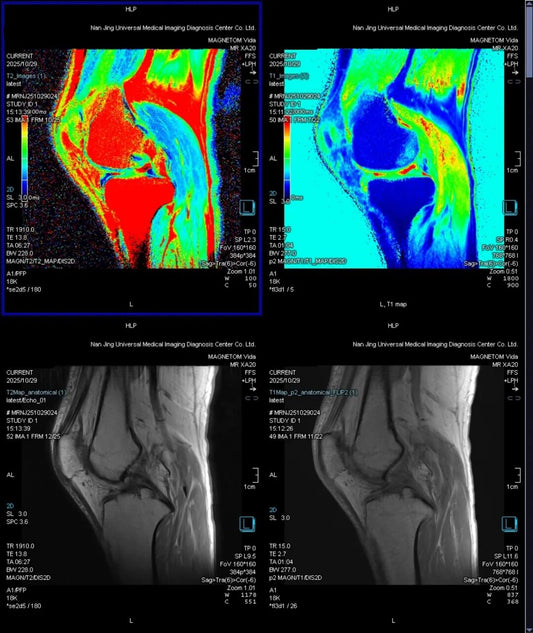

From Morphology to Composition: Beijing Radiolo...

Using $3.0T$ quantitative MRI ($T_{2}$-Mapping & $T_{1}$ Map), the Beijing Radiology Expert Team successfully localized "invisible" lesions by measuring biochemical shifts in the cartilage matrix, establishing a digital baseline for...